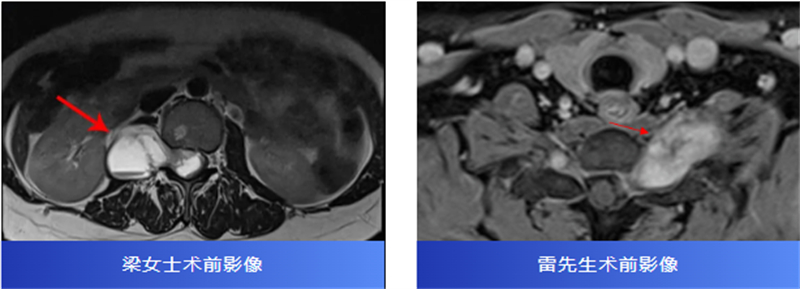

后來,經過腰椎磁共振檢查,才發現原來是椎管內長了一個腫瘤,壓迫著神經,并向外生長,延伸到了右腎附近,情況十分復雜。

兩名患者轉診至柳州市人民醫院后,脊柱外科主任、主任醫師胡巍博士迅速組織醫學影像科、麻醉科等多學科會診。團隊對腫瘤病變范圍、與神經的毗鄰關系進行周密評估,為每位患者制定個體化手術方案。

術中,在顯微鏡輔助下,醫生精細分離腫瘤與神經組織,小心翼翼解除壓迫,最終切除了腫瘤。病理報告也帶來好消息:兩人均為良性神經鞘瘤。

術后,梁女士的腰腿痛消失了,雷先生的頸肩脹痛也得到了緩解。兩位患者都保住了正常的神經功能,步入康復的新階段。